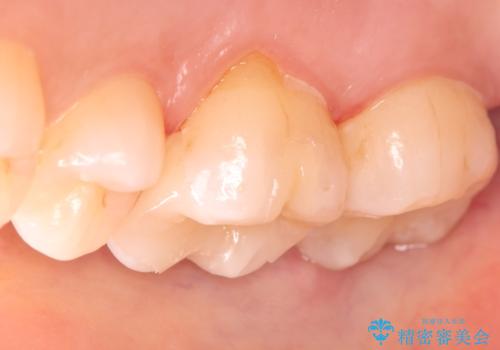

- 昔入れた金属の被せ物を白い物に変えたいと思い来院された患者様です。レントゲン等確認し審美的によく、強度のあるセラミックインレーにて治療いたしました。

審美的に良い補綴物に変わり満足いただきました。かみ合わせも問題なく快適に食事できているとのことでした。